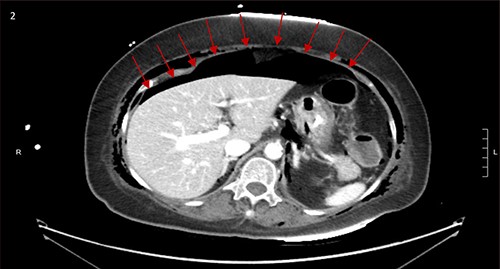

CT scan showed small bilateral pneumothoraces (Fig. 1a) in the setting of several mildly displaced anterior rib fractures with associated subcutaneous emphysema (Fig. 1b), as well as extensive intraperitoneal (Fig. 2), extraperitoneal and retroperitoneal (Fig. 3) air. However, imaging was negative for evidence of perforation. Given concern for abdominal compartment syndrome as evidenced by abdominal distension on exam, initially elevated peak pressures to 24 immediately following intubation, and CT findings of pneumoperitonum, the General Surgery service was consulted for evaluation and further assistance with management. On clinical exam, the patient’s abdomen was distended without tenderness, guarding, or rebound. Laboratory results were notable for white blood cell count of 21.1 per mm3, platelet count of 314 per mm3, and a whole blood lactate of 8.1 mmol/l. Her leukocytosis, though only mildly increased from her baseline of 15 over the previous days, was attributed to known Staphylococcus bacteremia for which she was on antibiotic therapy with a contribution from her shock and PEA arrest. Given the patient was hemodynamically stable with no signs of an acute abdomen, we decided to manage with serial abdominal exams without operative intervention. The patient was closely followed over the subsequent 5 days, during which time she remained stable; she no longer required pressors and was weaned to trach collar on post-arrest Day 2; her white blood cell count continued to downtrend and normalized post-arrest Day 7 as she remained on antibiotic therapy; no additional abdominal imaging was obtained, given her very benign abdominal exam. Operative management was never utilized and she remained asymptomatic. While in the intensive care unit, the patient improved and she was able to engage in physical and occupational therapy despite the pneumothoraces. She was discharged to a long-term acute care hospital on hospital Day 36.

(a) Bilateral anterior pneumothoraces; (b) moderate volume of subcutaneous emphysema in the anterior chest wall.